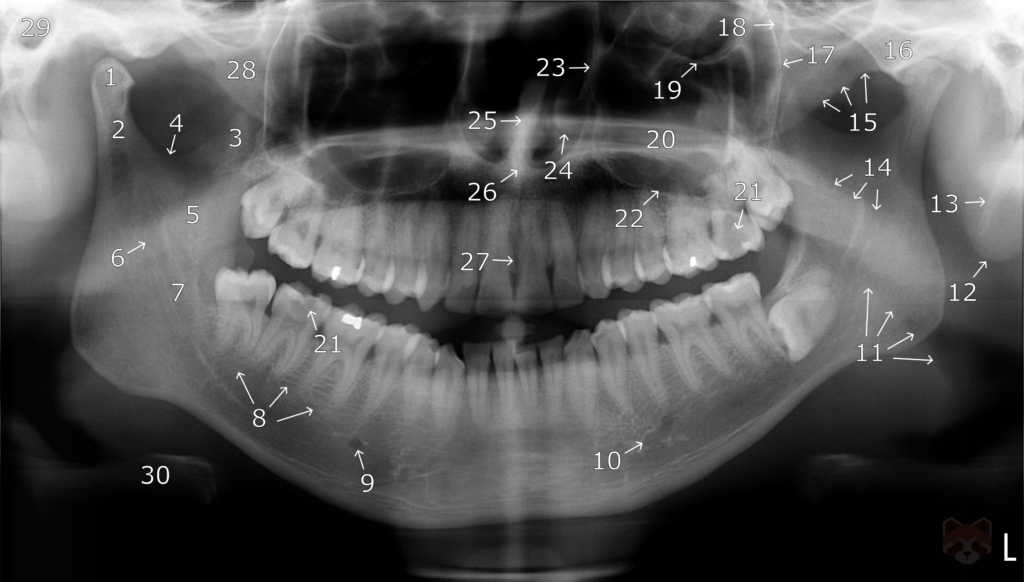

RADIOGRAPHIC ANATOMY

- Condylar head.

- Condylar neck.

- Coronoid process.

- Sigmoid notch.

- Mandibular ramus.

- Mandibular nerve foramen.

- Inferior alveolar nerve canal.

- Submandibular gland fossa.

- Mental nerve foramen.

- Anterior loop of the mental nerve.

- Dorsum of the tongue.

- Auricle (ear).

- Styloid ligament.

- Soft palate.

- Zygomatic arch.

- Articular eminence.

- Posterior wall of the maxilla.

- Pterygomaxillary fissure.

- Floor of the orbit, roof of the maxillary sinus.

- Hard palate.

- Occlusal caries.

- Floor of the maxillary sinus.

- Lateral wall of the nasal fossa, medial wall of the maxillary sinus.

- Inferior concha.

- Nasal septum.

- Anterior nasal spine.

- Incisive (nasopalatine) canal.

- Pterygoid plates.

- External auditory meatus.

- Hyoid bone.

- Nasopharyngeal airspace – posterior to the nasal cavity.

- Palatoglossal airspace – between the palate and the tongue.

- Glossopharyngeal airspace – posterior to the tongue and oral cavity.

- Maxillary sinus floor.

- Extruded gutta-percha.

- Lamina dura.

- Bony trabecula.

- Internal restorative void.

- Enamel of the disto-lingual cusp of the maxillary first molar.

- Film holder